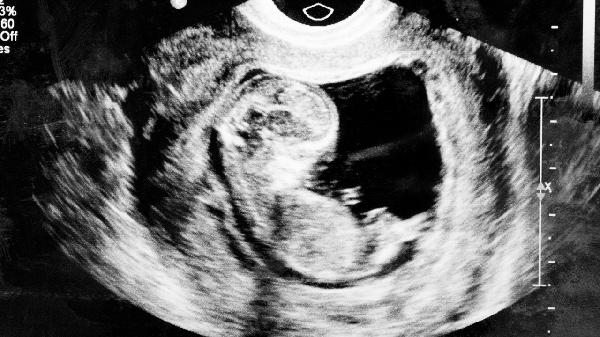

孕期常规B超检查主要用于监测胎儿生长发育情况,评估胎盘位置及羊水量等指标。临床常用的二维B超采用低频超声波,声波能量严格控制在安全阈值内,单次检查时间通常不超过30分钟。现有研究未发现诊断剂量超声波与胎儿畸形、发育迟缓存在明确关联。医疗机构会遵循最小剂量原则,由专业医师操作设备,避免同一部位长时间聚焦扫描。